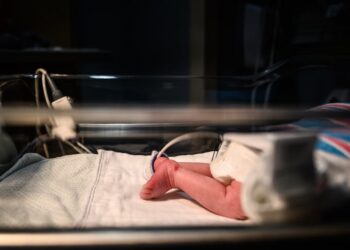

Virtually every living thing on Earth, from Patagonian penguins to newborn human babies, has been touched by the synthetic chemicals...